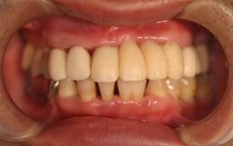

治療中

抜歯、インプラント、再生療法を行い、仮歯で様子をみてます。○○さん。もうすこしです。頑張りましょう。